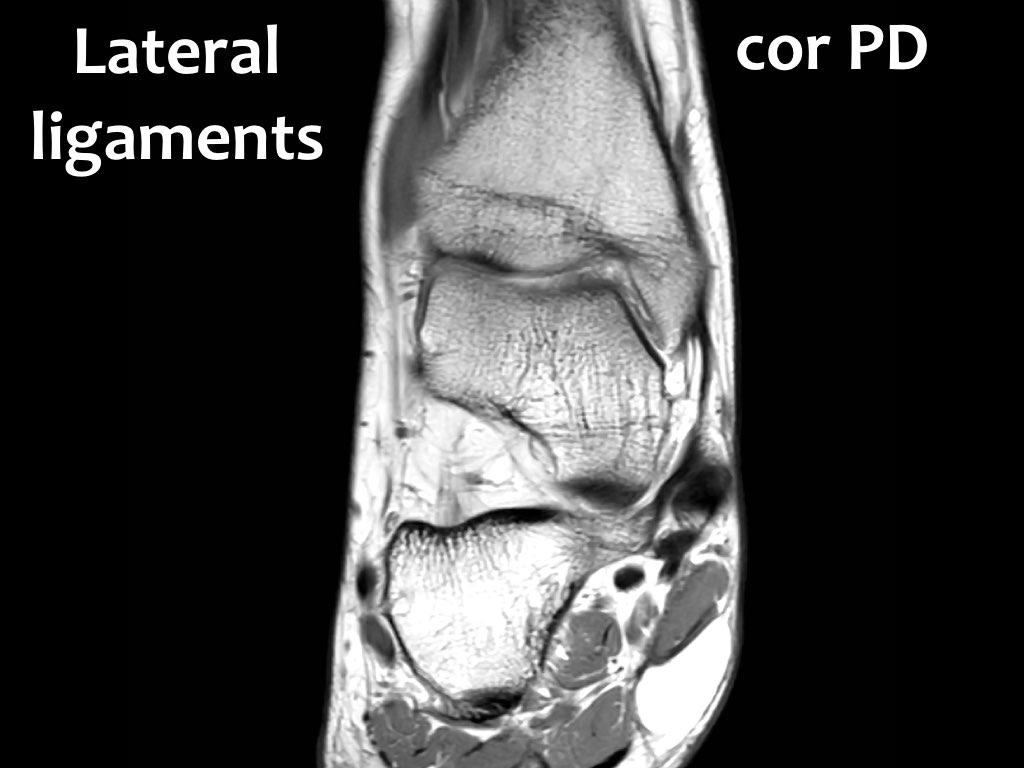

Có ba dây chằng ở phía ngoài:

- Dây chằng sên mác trước (anterior talofibular ligament – ATFL)

- Dây chằng gót mác (calcaneofibular ligament – CFL)

- Dây chằng sên mác sau (posterior talofibular ligament – PTFL).

Cuộn qua các ảnh cắt vành.

Bạn có thể phóng to ảnh bằng cách nhấp vào.